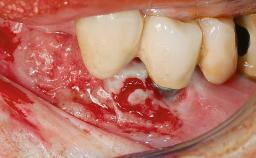

A male patient had lost teeth 11 and 22 as a result of a bicycle accident at age 14. In his adolescent years, a removable prosthesis had replaced the missing teeth. At age 21, the patient was referred by his dentist to the university clinic for treatment of the missing teeth 11 and 22 with implants. He was in good health and a nonsmoker. The absence of teeth 11 and 22 over many years had led to significant atrophy of the alveolar ridge, particularly at site 11. As a first step, the alveolar ridge was augmented using a block graft to replace the lost bone. A Straumann SP implant (diameter 4.1 mm, length 12 mm; Institut Straumann AG, Basel, Switzerland) and a Straumann Narrow Neck implant (length 10 mm) were inserted in the correct location and axial position at sites 11 and 22, respectively, six months later. After three months of healing and subsequent reentry, the patient returned to the referring dentist to receive the prosthetic restoration. The patient was seen again six months after the restoration had been placed. The frontal view showed a high smile line, an irregular gingival profile, and a bluish-gray tinge to implant crowns 11 and 22 compared to the natural dentition.